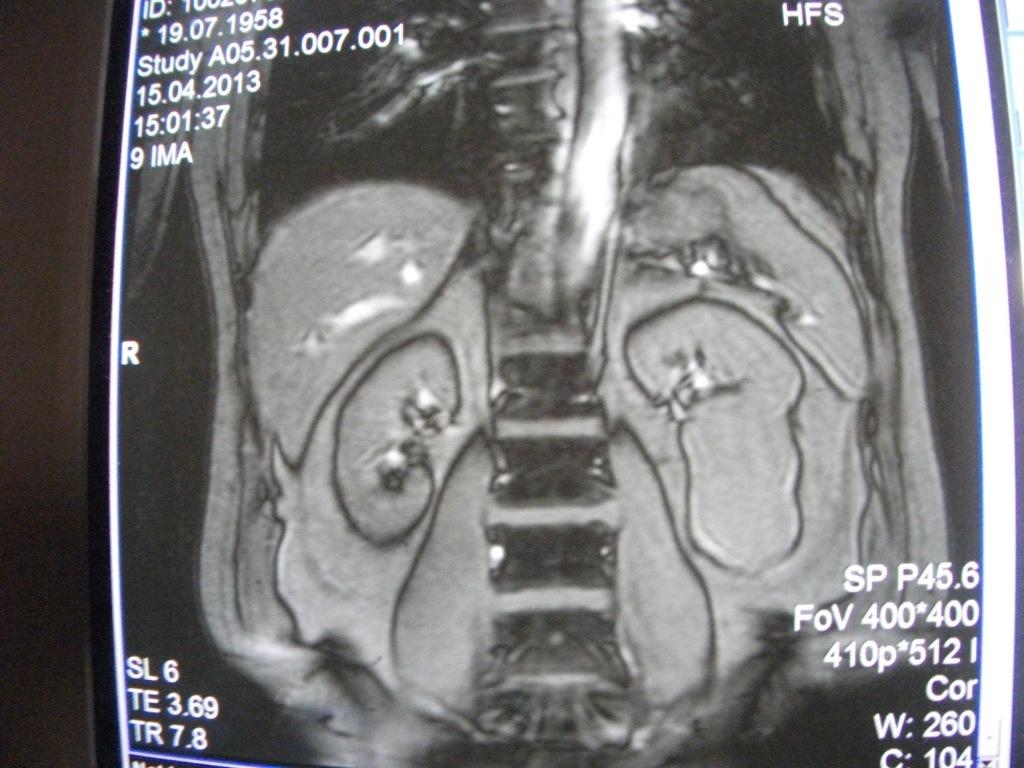

такое заключение: Левая почка: расположена обычно, увеличена, общими размерами около 13х5,5см. В области средней и нижней трети почки определяется объёмное образование неправильной формы, деформирующее наружный контур почки, распространяющиеся с чашечно-лоханочную систему. Опухоль имеет четкие неровные бугристые контуры с наличием псевдокапсулы, неоднородной структуры с признаками распада, максимальными размерами около 78,7х47х48мм